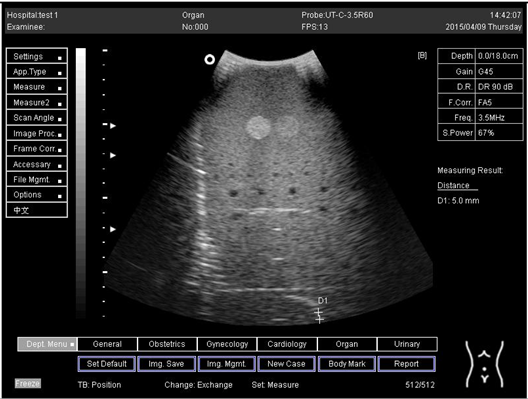

Table A3. The distance for axial and lateral resolution in mm for depth of 14.0, 16.0, 18.0 and 24.0 cm depth for curve probe at surface 4.

Depth (cm)DiagramDistance (mm)

14.0Axial resolution

Biomimetics 07 00130 i023

D1 = 4.9

D2 = 4.2

Lateral resolution

Biomimetics 07 00130 i024

D1 = 5.0